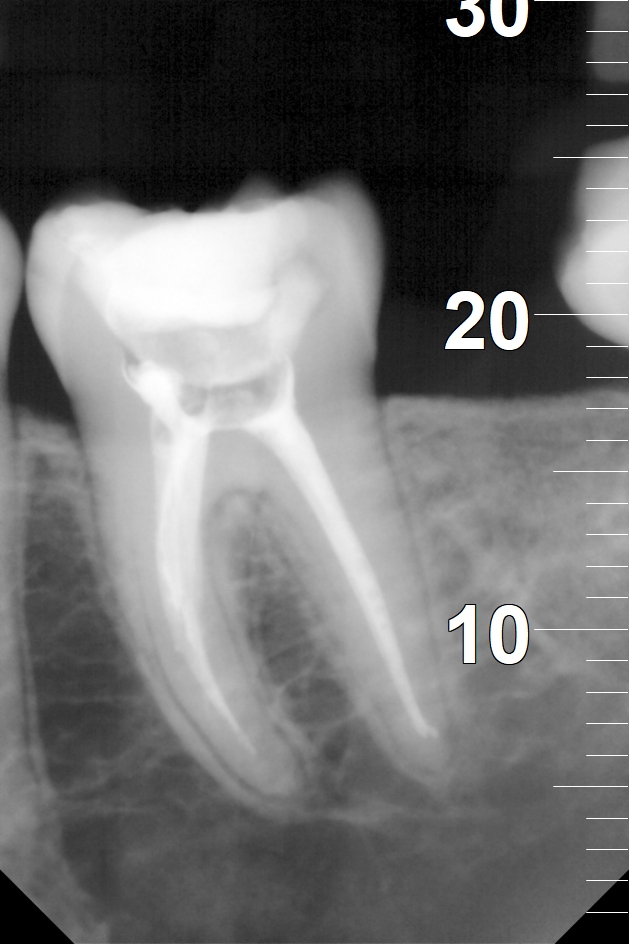

Na nasledujúcich RTG snímkoch sú dobre viditeľné biele výplne ošetrených koreňových kanálikov. Biela farba na snímkoch je spôsobená tým, že výplňový materiál je zámerne RTG kontrastný, aby bolo ľahko možné identifikovať výplne koreňových kanálikov.

Zaplnené korene zuba číslo 36.